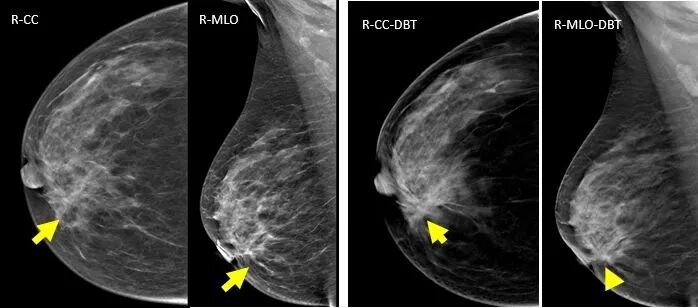

病例2:CC,MLO/DBT显示:肿块、形态、边缘、密度、大小显示显著优于MG,特别是肿块周围晕环显示清晰,对于良恶性病变的鉴别颇具意义。病理:乳腺纤维腺瘤。

病例3、病例4:CC,MLO/DBT显示:肿块、形态、边缘、密度、大小显示显著优于MG,周围毛刺征显示清晰明显。病理:乳腺浸润性导管癌。